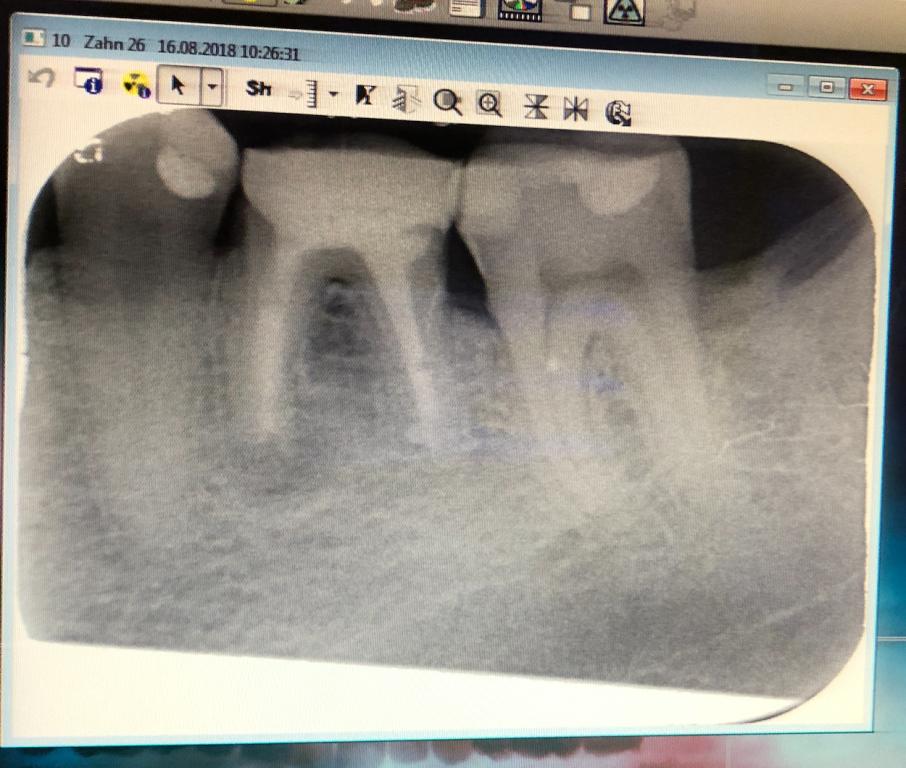

Оба зуба под коронками с пару лет. Появилась некая легкая чувствительность при легком надавливании. Так, время от времени, разово и беспричинно.

Лечящему врачу картинка не понравилась. Думает, что с этим делать (пока другим занимаемся).

Что скажете ?

...медиальный корень шестого зуба с гранулемой...открыть каналы, перелечить... и будет Вам счастье...)))